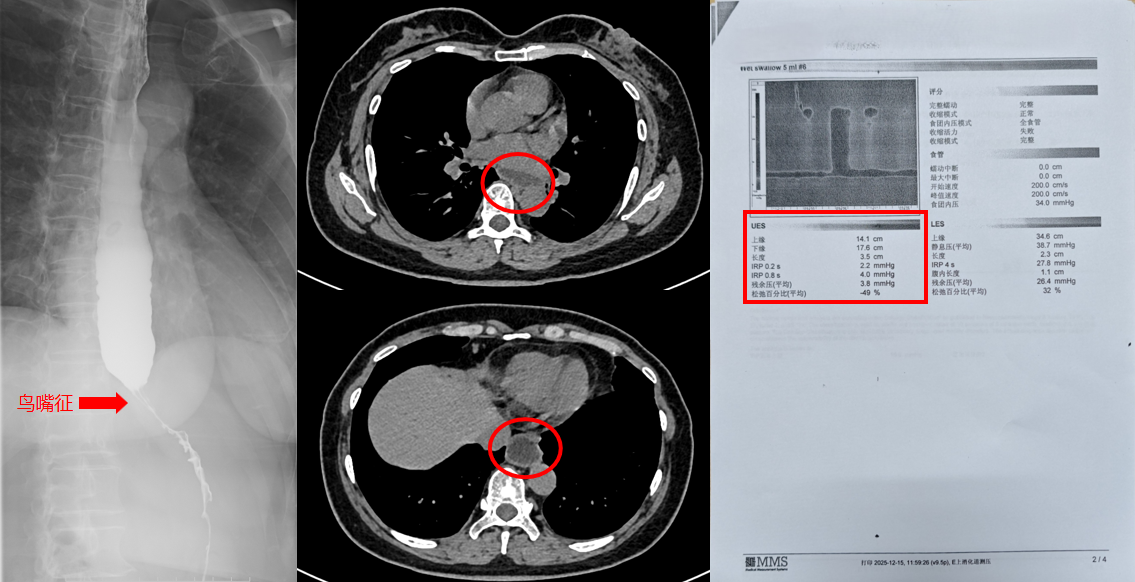

辗转来到西安市第四医院就诊,经详细检查后,最终确诊为罕见的:贲门失弛缓症Ⅱ型。贲门失弛缓症是一种罕见病:作为一种原发性食管动力障碍性疾病,其发病率较低,临床诊断需结合典型症状、影像学及食管测压检查,易与普通胃食管反流病、食管肿瘤等混淆,确诊难度较大。

食管下括约肌松弛不全,食管体部蠕动消失,导致食物无法顺利通过贲门进入胃内,形成“梗阻-潴留-反流”的病理循环。患者以进行性吞咽困难为核心症状,常伴随食物反流、呕吐、体重下降,严重时可出现吸入性肺炎、营养不良等并发症,严重影响患者生活质量。

看到王阿姨的情况,胸科病院胸部疾病诊疗中心张潍教授团队立即为根据王阿姨的病情严重程度、身体状况制定个体化微创手术方案:胸腔镜下Heller肌切开术,联合胃底折叠术。

这种手术虽然技术难度大,但能在解除梗阻的同时可以建立抗反流屏障,长期疗效稳定,是治疗复杂病例的优选方案。明确了方案之后,胸科病院张艰院长组织了胸外科、麻醉科、营养科、康复科组建MDT团队,共同制定了完善的:个体化微创治疗流程。